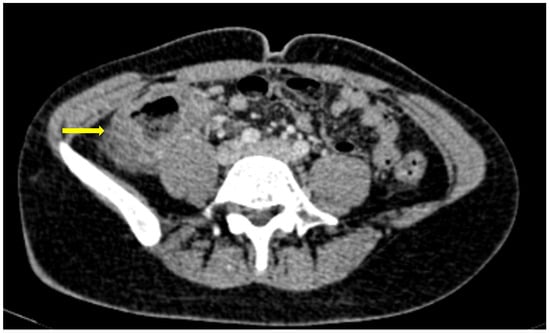

Figure 3. 55-year-old male patient with COVID-19 pneumonia with right lower quadrant pain. CT on admission demonstrating a thickened appendix and proximal fat stranding (yellow arrow), indicating acute appendicitis.

Figure 4. A 48-year-old female patient with COVID-19 pneumonia and no other comorbidities. CT scan depicted a thickened cecum with proximal fat stranding (yellow arrow).